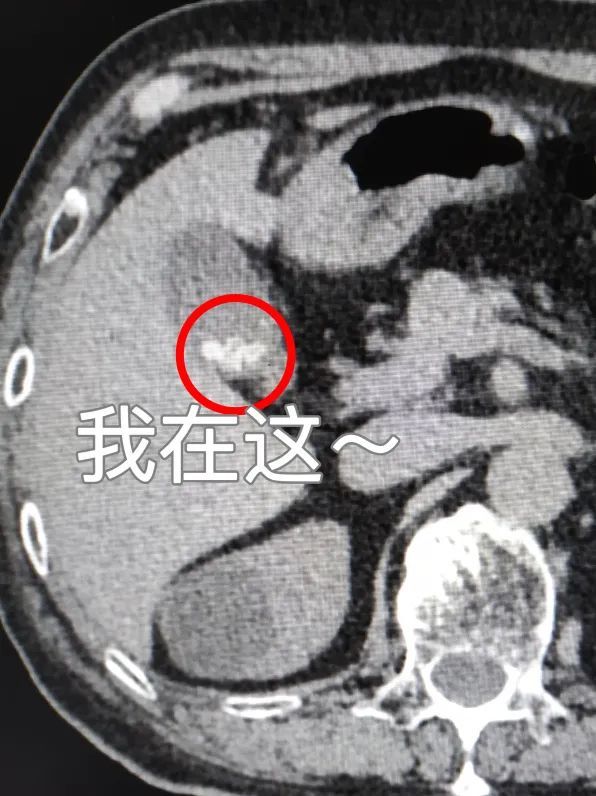

胆囊阳性结石

胆囊阳性结石就是胆色素类结石(CT上表现为高密度):CT表现为高密度,CT值在50Hu以上,单发或多发,形态、大小各异,泥沙样结石常沉积在胆囊下部,呈高密度,与上部胆汁形成液平面。